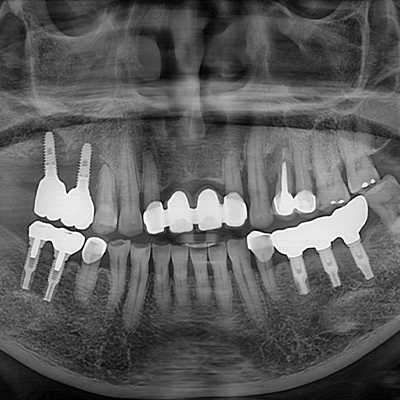

재수술 임플란트란?

재수술 임플란트는 이미 식립된 임플란트에 문제가 발생하여 제거하고 다시 시술하는

고난이도 치료를 말합니다. 임플란트의 보급은 빠르게 늘어났지만, 그로 인해 수명을 다해

부러지거나 잇몸 질환으로 인해 제거되는 임플란트도 많아졌습니다.

일반적으로 수직적으로 50% 이하의 염증이라면, 제거하지 않고 잇몸치료로 유지가 가능합니다.

하지만 심각한 염증이나 임플란트 실패의 경우에는 제거 후 재수술이 필요합니다.